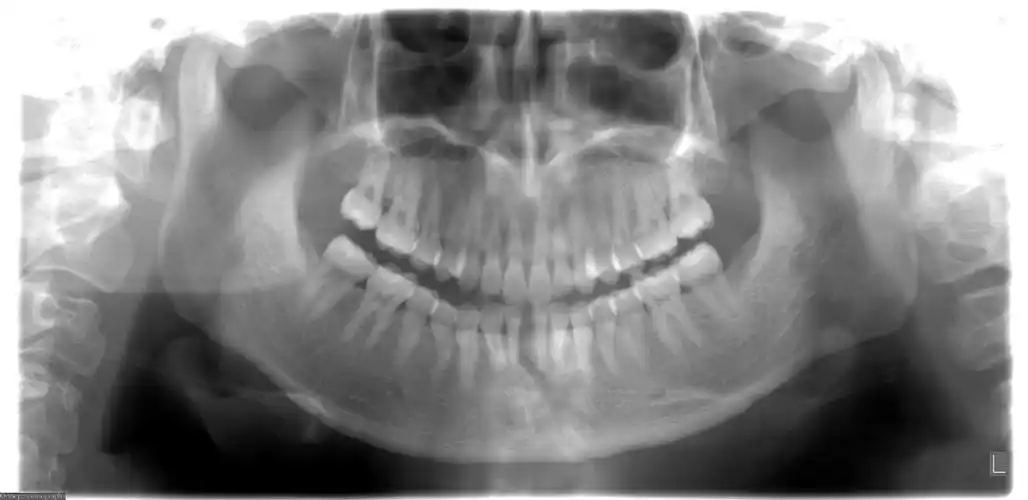

颏部线性骨折